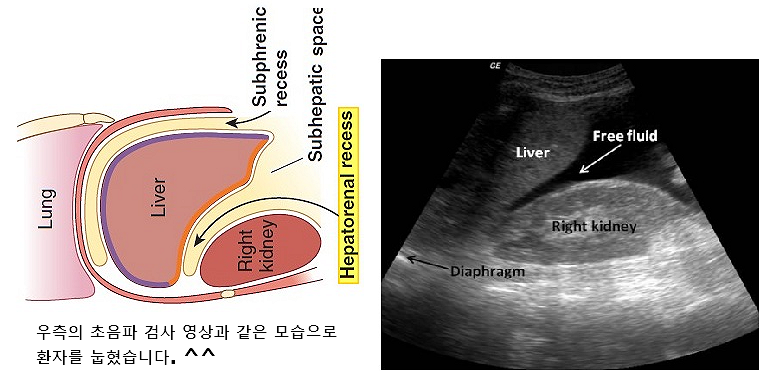

- 임상을 공부하게 되면 'dependent position'이라는 말이 자주 나오는데 특정 자세에서 몸안에 제일 낮은 부위를 뜻합니다.

예를 들어서 (환자가 아파서, 검사를 받기 위해) 누워 있는 자세에서는

1) 폐의 dependent position은 주로 lower lobe의 superior segment가 되고,

제일 낮은 위치이기 때문에 주로 흡인성 폐렴이 생기는 곳이 됩니다.

2) 배에서는 간과 콩팥사이가 되고 → Hepatorenal recess

3) 골반에서는 자궁과 직장사이가 됩니다 → rectouterine pouch(cul-de-sac)

- 임상적인 의미는 배나 골반에서 염증성 질환, 장기의 출혈등이 의심되는 경우에,

초음파 검사를 의뢰받은 영상의학과 의사는, 복막공간 & 골반공간에서 염증으로 인한 비정상적 물(fluid collection) 이나 출혈(hemorrahge)이 생겼는지를 초음파로 찾게 되는데, 이때 노련한 의사는, 배의 공간(복강, peritoneal cavity), 골반의 공간(골반강, pelvic cavity)에서 물이 제일 먼저 고일 수 있는 낮은 위치(dependent postion or pouch)에, 초음파를 우선적으로 검사해 보게 됩니다.

→ 당연히 검사의 시간을 단축하고 효율이 올라가겠죠 ^^.

우측 초음파 사진에서, 상당의 많은 양의 abnormal fluid collection이 hepatorenal recess에 보입니다.